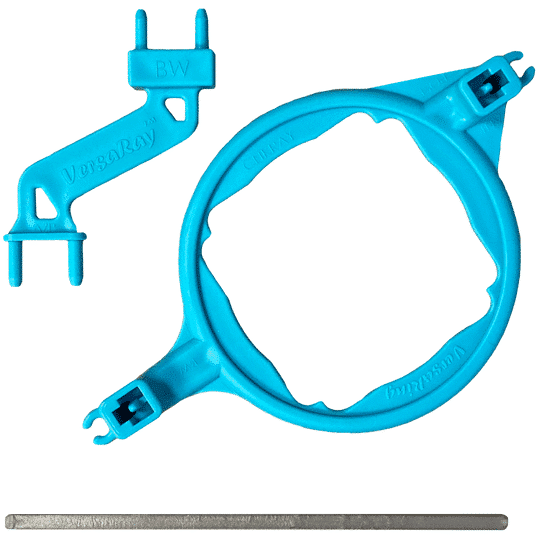

The VersaRay™ sensor positioning kit is a lightweight, easy-to-use single ring and rod system for your DentiMax Dream Sensor. It is the only holder that works with any X-ray system or popular handheld units such as Nomad™ and MaxRay™. Unlike other X-ray holder rods, the VersaRay™ rod allows the user to align the ring as close as possible to both the patient and scattershield. Best of all, an entire FMX radiographic series can be taken with just one rod, one ring – one DentiMax VersaRay™. Includes VersaRay™ holder, ring, and plastic rod. […]

The VersaRay™ sensor positioning kit is a lightweight, easy-to-use single ring and rod system for your DentiMax Dream Sensor. It is the only holder that works with any X-ray system or popular handheld units such as Nomad™ and MaxRay™. Unlike other X-ray holder rods, the VersaRay™ rod allows the user to align the ring as close as possible to both the patient and scattershield. Best of all, an entire FMX radiographic series can be taken with just one rod, one ring – one DentiMax VersaRay™.

Includes VersaRay™ holder, ring, and plastic rod.